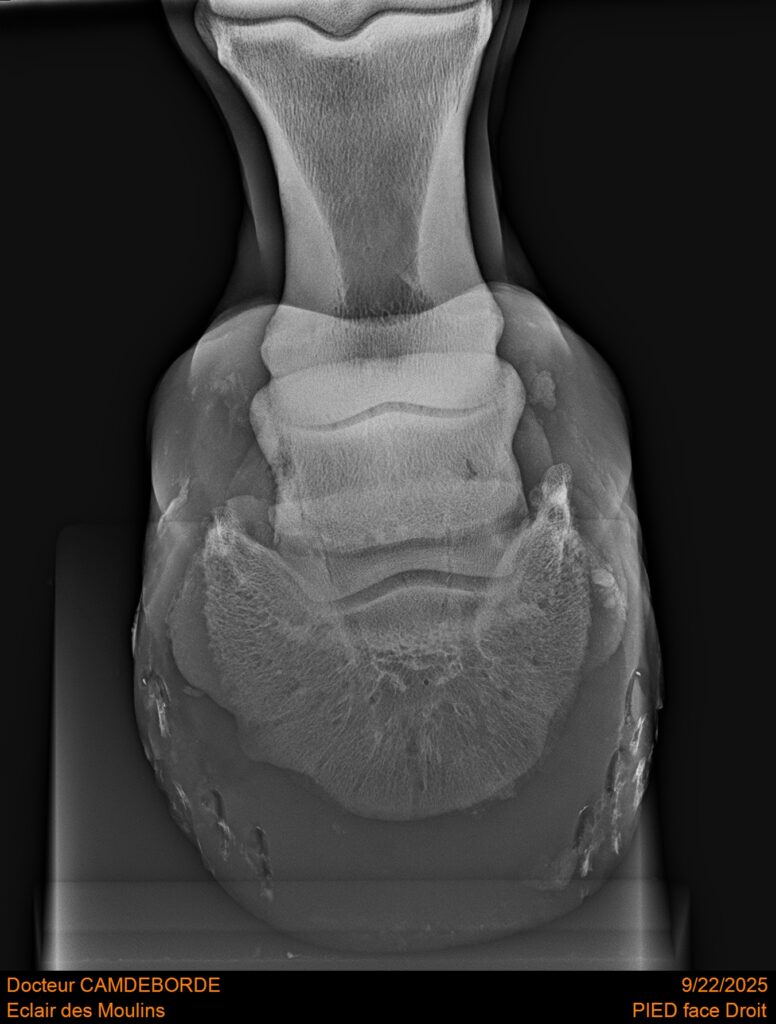

RADIOS ET CLINIQUE